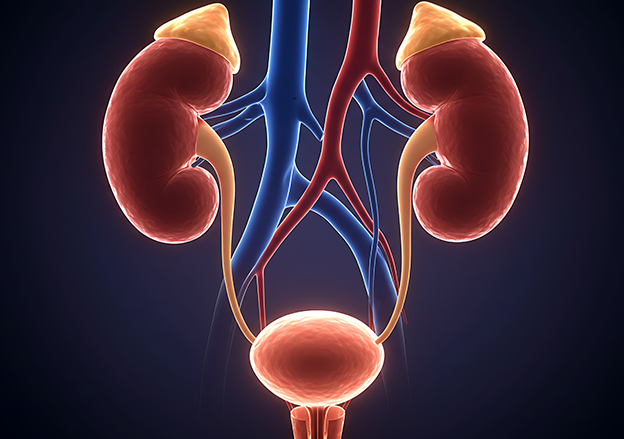

Komplettfrüherkennungsuntersuchung des Mannes

inkl. Sonographie der Prostata, der Nieren und der Harnblase sowie

PSA-Bestimmung, Urinuntersuchung und schriftlichen Befund: € 158,63

Nierencheck für Mann und Frau in Form einer Ultraschalluntersuchung

beider Nieren und der Blase: € 80,42